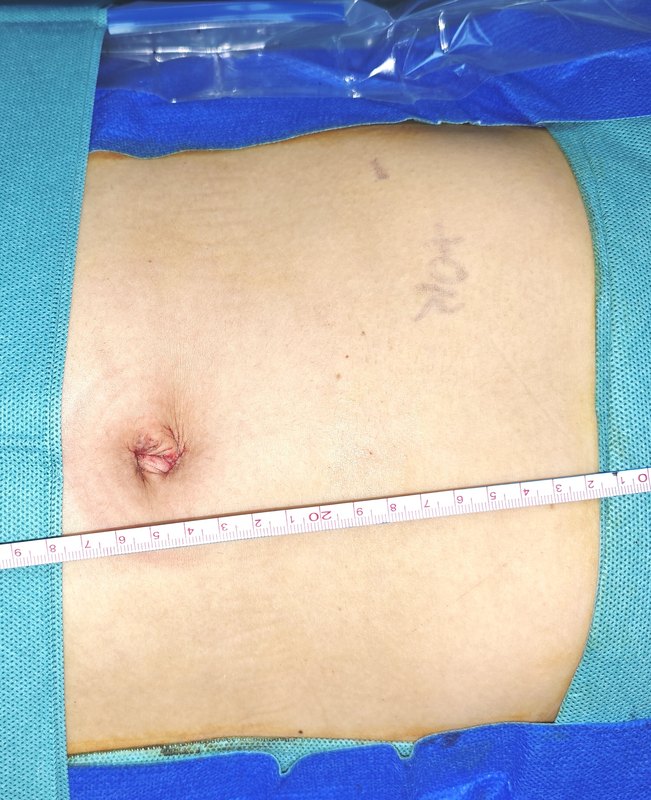

單孔腹腔鏡膽囊切除術(shù)是一種先進的微創(chuàng)手術(shù)。它只需一個小切口,相較于傳統(tǒng)手術(shù),大大減少了創(chuàng)傷。術(shù)后疼痛更輕、恢復更快,疤痕微小幾乎看不見。能讓患者在短時間內(nèi)回歸正常生活,為膽囊疾病患者帶來更優(yōu)質(zhì)的治療選擇。

治療前 患者因右上腹疼痛2月入院。查CT提示膽囊底部占位,36*35mm,不除外膽囊癌可能。腫瘤標志物正常。術(shù)前按膽囊癌術(shù)前準備。 治療中 術(shù)中發(fā)現(xiàn)膽囊底部較大腫塊,完整切除膽囊,完整取出。膽囊底部囊壁明顯增厚。術(shù)中快速病理為膽囊腺肌癥。 治療后 治療后1天 患者今天術(shù)后第一天,恢復飲食,下床活動。